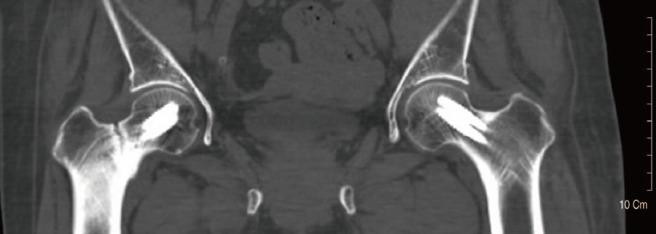

A 78-year-old woman developed an insufficiency fracture on her right femoral neck without trauma after four years of treatment with a bisphosphonate. Her fracture was fixed by two screws and her anti-osteoporotic drug was changed from an anti-resorptive to an anabolic agent. Seven months later, however, she sustained similar insufficiency fracture on the left femoral neck and was treated with the same method. She developed right inguinal pain again approximately eight months after her right side operation. The results of imaging tests revealed that her insufficiency fracture was converted to complete fracture, and that the fracture gap had widened as well. Her right hip was revised with hemiarthroplasty. A histological exam of the fracture site revealed evidence of decreased bone healing. Long-term administration of anti-resorptive drug prevents bone healing and remodeling and can result in atypical fractures of the femoral neck. Osteosynthesis was difficult to accomplish despite the application of proactive fixation. Therefore, more rigid fixation and careful postoperative treatment should be considered.

摘要